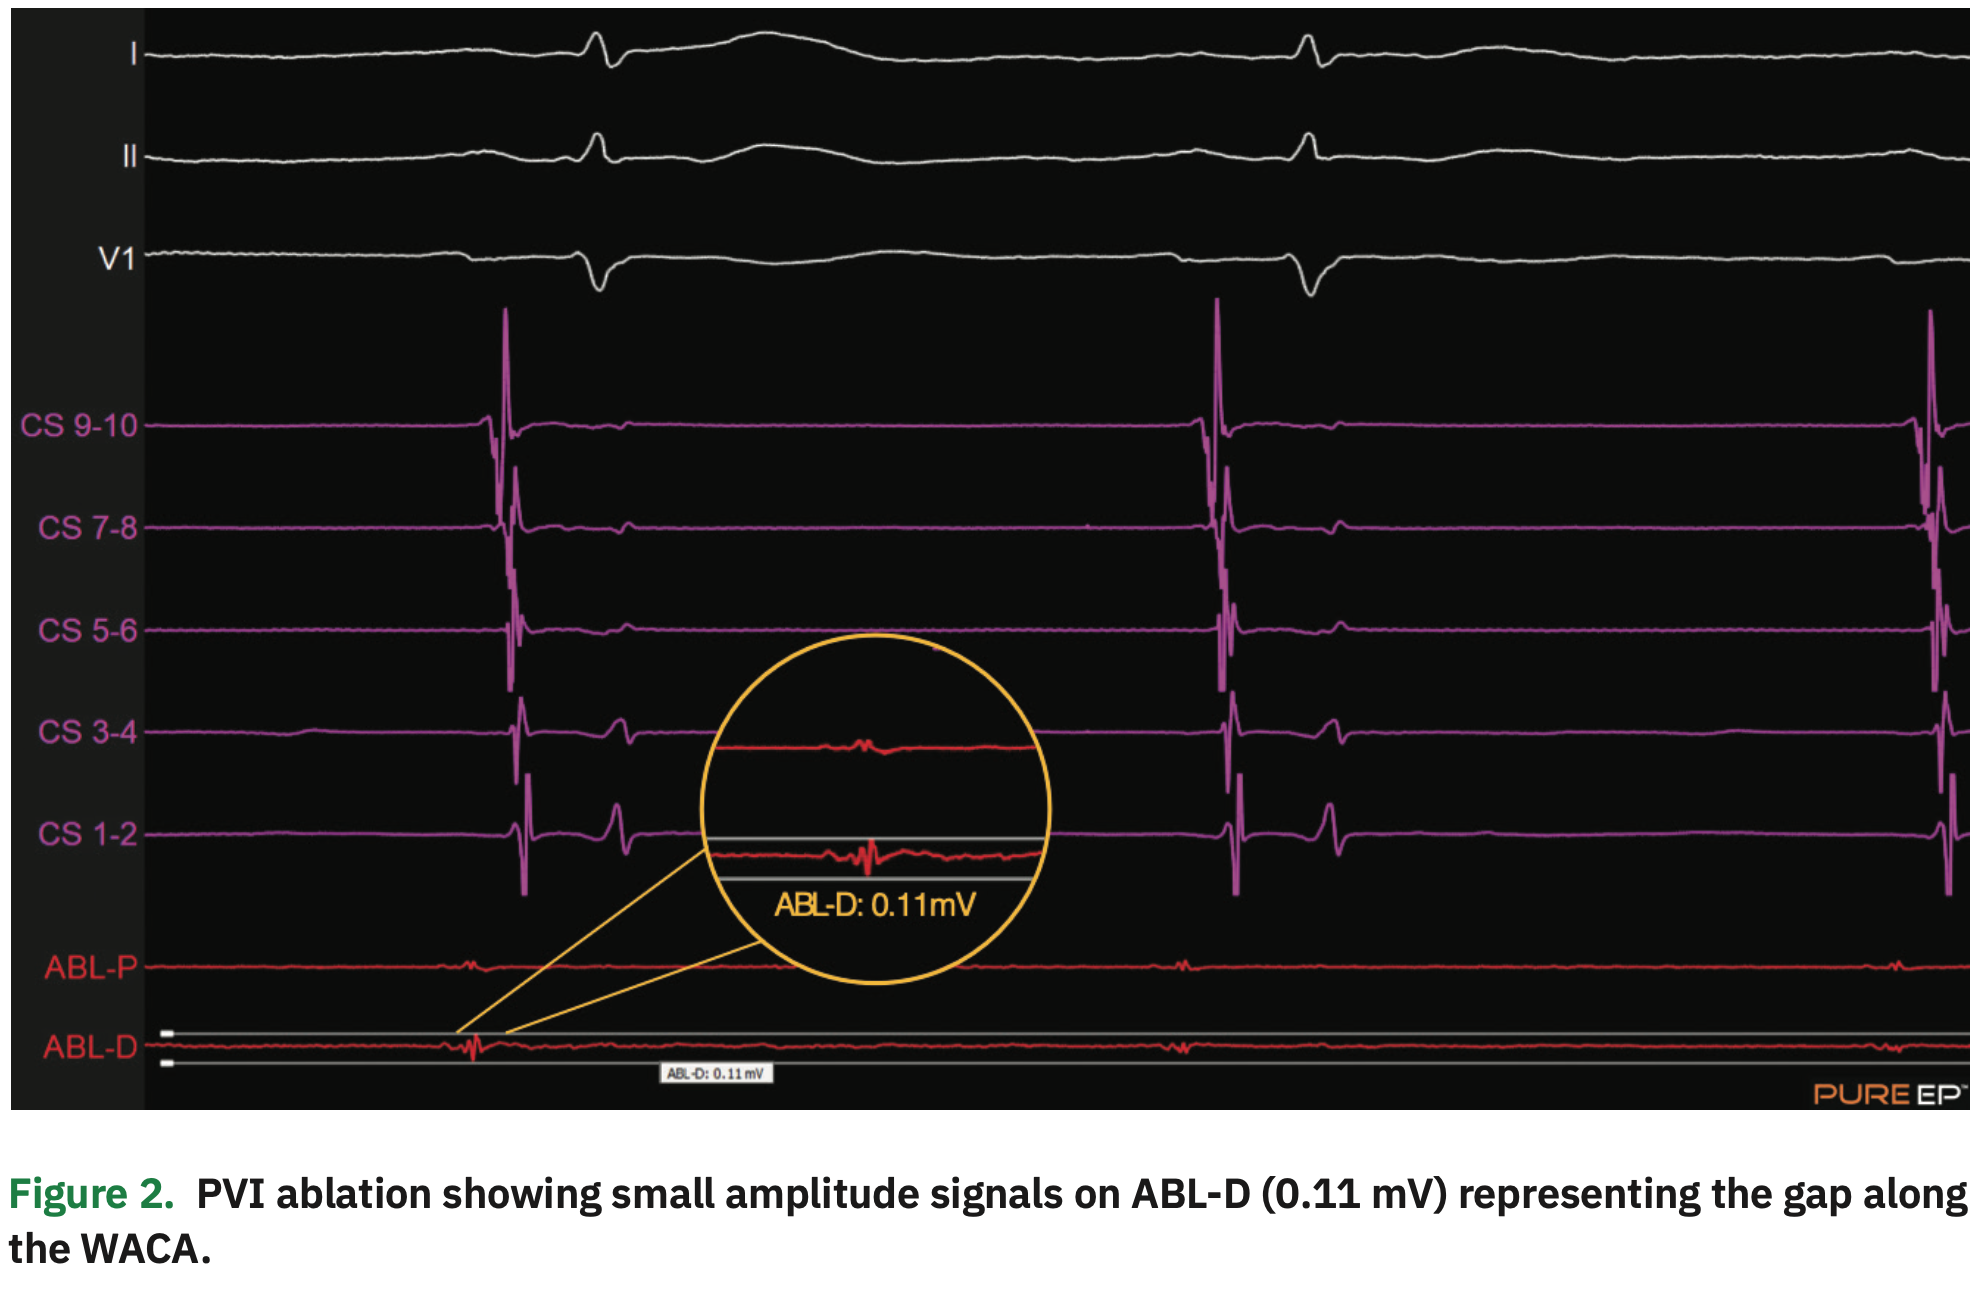

As far as my clinical decision-making process, I’ve noticed since adding the PURE EP™ System that during PVIs, I have a better sense of when I’ve completely isolated the veins. I’ve observed a higher occurrence of “first-pass” pulmonary vein isolations since using the PURE EP™ system. When the PV potentials on PURE EP™ go flat, I feel more confident I’m done with that ablation, so it has actually increased my ablation efficiency.

Yes. Oftentimes, during PVI procedures, it can be difficult to find areas of connection or reconnection, because we just ablated around the pulmonary veins where the signals are very low voltage. Using the PURE EP™ System during PVI procedures, I was able to achieve “first-pass” isolation. PURE EP™ was very helpful in identifying those areas.